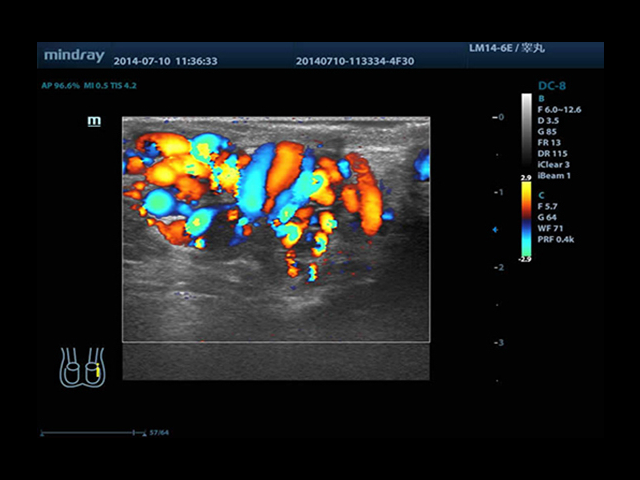

Mindray DC-8 Exp оснащен новым поколением датчиков с увеличенным количеством элементов и инновационной технологией "3T". Это позволяет достичь высокой детализации и качества изображения. Благодаря новейшей технологии iFlow, можно визуализировать даже самые мелкие сосуды и кровеносные пути.

Сверхширокополосная нелинейная обработка изображений снижает визуальные шумы на 30% по сравнению с другими системами. Технология iClear позволяет устранить зернистость изображения, а iBeam (технология пространственного компаундинга) обеспечивает высокое качество сканирования органов и тканей под различными углами.

• Natural Touch Elastography - опция оценки эластичности ткани (эластография), с программой анализа. Действует на линейных и внутриполостных датчиках. Компрессионный метод.